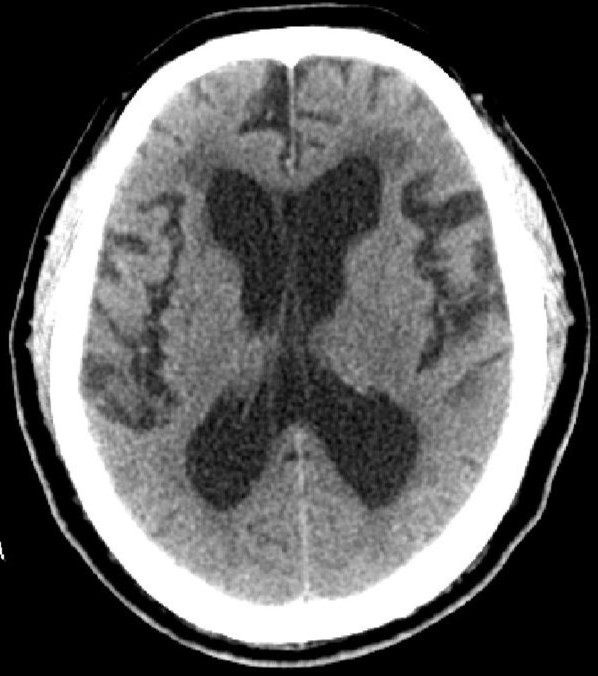

因為腦脊液的分泌、或循環(huán)、或吸收過程中出現(xiàn)障礙,則會產(chǎn)生腦積水。腦積水致腦脊液的容積增大,導致腦血流量及腦組織受壓并容積減少。臨床分類多樣:嬰幼兒腦積水和成人腦積水;高壓性腦積水和常壓性腦積水;腦室內(nèi)腦積水和腦外腦積水;癥狀性腦積水和無癥狀性腦積水;進行性腦積水和靜止性腦積水。比較常用的是按病因分類:交通性腦積水和阻塞性腦積水。其中交通性腦積水病因:腦脊液吸收功能障礙、蛛網(wǎng)膜顆粒發(fā)育不良、腦脊液成份改變或濃縮及腦脊液分泌過多;阻塞性腦積水病因:中腦水管狹窄或閉塞、Dandy-Walker綜合征、小腦扁桃體下疝畸形、炎癥或出血、顱內(nèi)占位性病變等。臨床癥狀:嬰幼兒有發(fā)育延遲、頭顱增大、行走障礙等;成人可有神志及精神變差、記憶力下降、頭痛頭暈、行走困難或二便失控等。頭顱CTMR可以明確診斷及辨別病因。治療主要以手術(shù)治療為主。絕大多數(shù)患者愈合良好。(神經(jīng)外科 龍青山)

正常頭顱CT          頭顱CT示腦積水